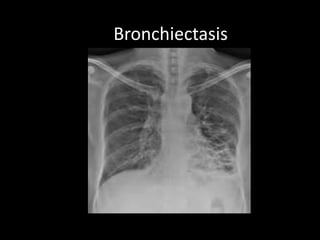

Bronchiectasis

Varicose Cystic cylindrical